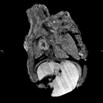

| Serial 2D EFIC image stack in the coronal plane of 2459-006-1 (E16.5) shows DORV, AVSD, RV non-compaction, LV hypertrophy, and cushion-like valves

Click thumbnail to play movie. | b2b2459Clo/b2b2459Clo | C57BL/6J-b2b2459Clo |